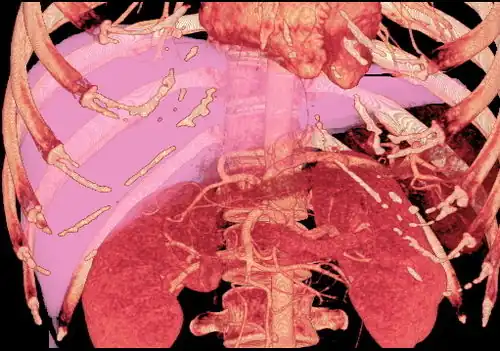

Couinaud classification system

Shape of human liver in animation, with eight Couinaud segments labelled

In the widely used Couinaud system, the functional lobes are further divided into a total of eight subsegments based on a transverse plane through the bifurcation of the main portal vein.[30] The caudate lobe is a separate structure that receives blood flow from both the right- and left-sided vascular branches.[31][32] The Couinaud classification divides the liver into eight functionally independent liver segments. Each segment has its own vascular inflow, outflow and biliary drainage. In the centre of each segment are branches of the portal vein, hepatic artery, and bile duct. In the periphery of each segment is vascular outflow through the hepatic veins.[33] The classification system uses the vascular supply in the liver to separate the functional units (numbered I to VIII) with unit 1, the caudate lobe, receiving its supply from both the right and the left branches of the portal vein. It contains one or more hepatic veins which drain directly into the inferior vena cava.[30] The remainder of the units (II to VIII) are numbered in a clockwise fashion:[33]